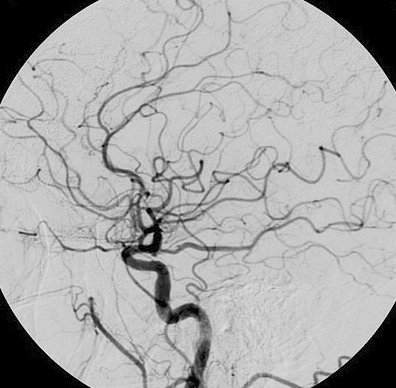

Digital subtraction angiography (DSA)

An imaging method that allows real-time visualization of the patient’s arteries.

It involves taking a series of x-rays at timed intervals while injecting radiopaque IV contrast. The pre-contrast images are then digitally subtracted from the images taken with IV contrast to visualize the artery of interest.

Indication: coronary angiography (cardiac catheterization), visualization and treatment (stents) of cerebral aneurysms and peripheral arterial disease (highest diagnostic accuracy)